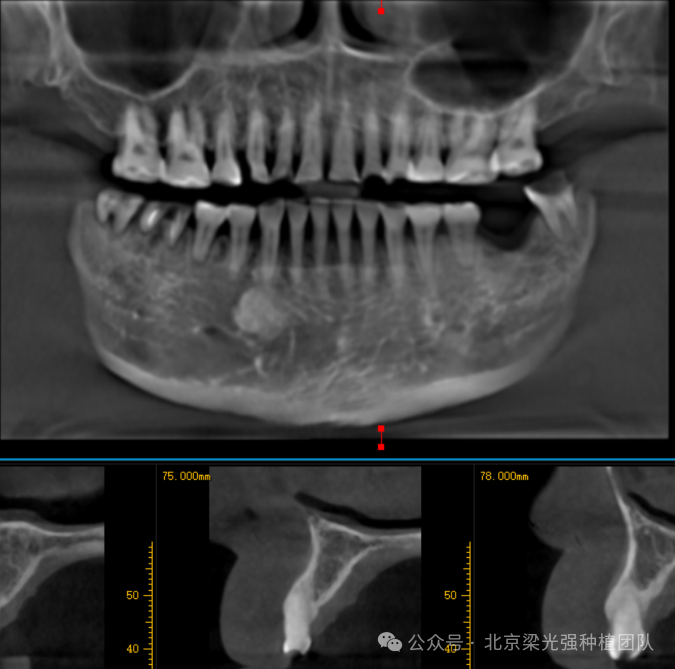

口内检查:四环素牙,前牙反合并且伴有重度磨耗,46、47残根,由于重度磨耗和反合关系,颌间距变低,修复空间不足,12-22II度松动,X光显示牙根较短,骨支持少,骨质初步判断为四类骨,

术前CBCT:

术后CBCT: